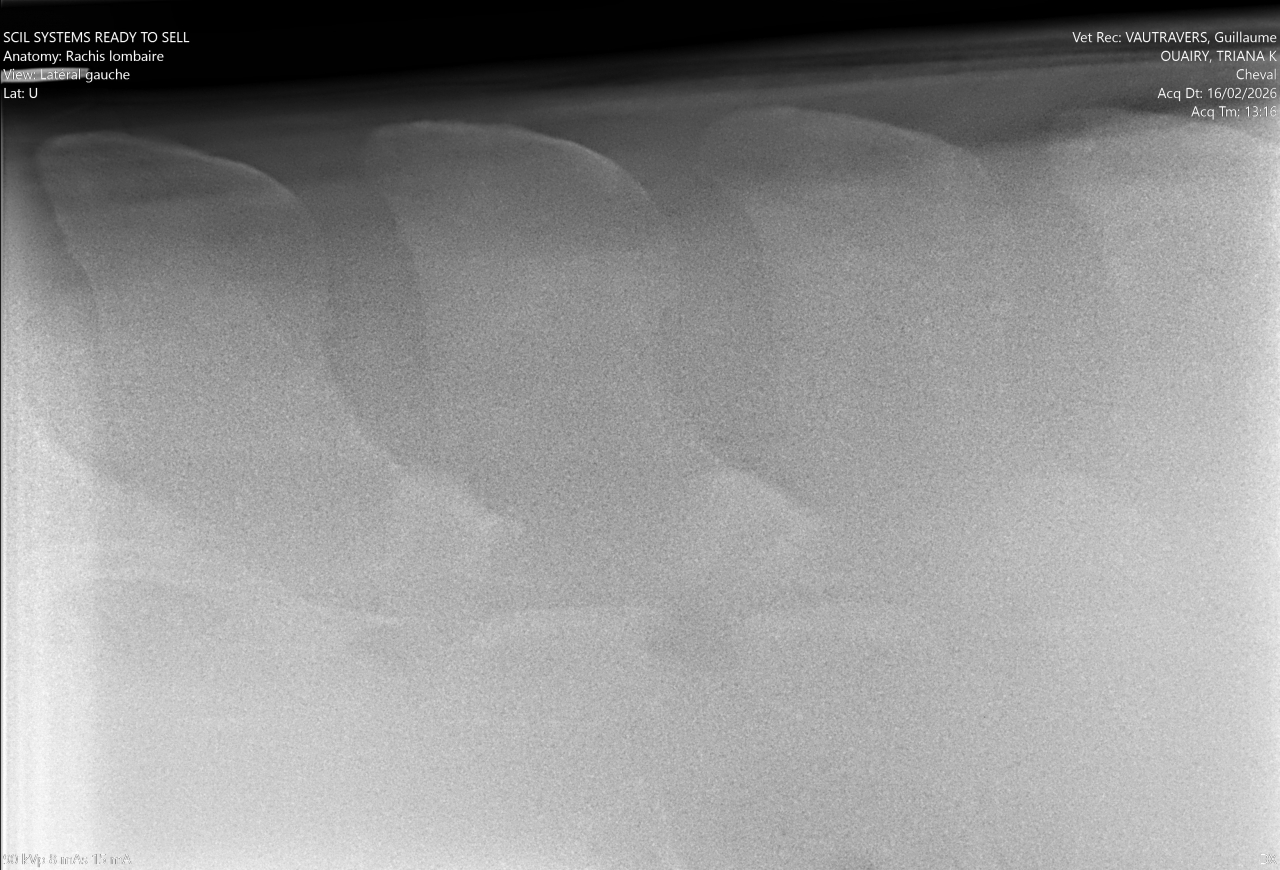

| Dire merci | Bonjour à tous, Ce forum est une mine d'or et peut-être que quelqu'un aura une piste, une idée ou des pouvoirs magiques pour nous aider (oui, j'en suis à ce stade). Ma jument, qui prend 7 ans cette année, ne peut plus tourner à droite au trot. Petit récap de sa vie : Je l'ai acheté à 1 an. Elle avait déjà une démarche particulière des postérieurs mais à la visite véto, on a contrôlé les grassets et RAS. Les vétos ont mis ses allures sur le compte de la croissance. Princesse grandit et chaque année, elle rencontre un problème (blessure, infection bactérienne, problème divers et varié). Je commence le débourrage en extérieur à l'âge de 4 ans mais monte très très peu. A 5 ans, je termine le débourrage aux 3 allures en extérieur mais le travail reste très léger. Je sens déjà que le trot n'est pas son fort. Elle est plus confortable au galop. 6 ans, grave accident ou elle reste couchée des heures sur son côté droit, qui nécrose complètement. On arrive à la fin des 6 ans, je la change de pension, la met au travail en carrière. Une jument qui va beaucoup mieux, qui travaille bien, qui change physiquement. 3 mois de paix. 3 mois ou je me dis : "enfin on va pouvoir profiter". Mais non, fin décembre, elle commence à se défendre quand je monte. Je sens une gène physique mais peut-être que la mise au travail ne lui plait pas. J'axe sur l'extérieur mais les défenses sont aussi présente. Elle refuse de trotter (je peux marcher et galoper). Petit à petit, l'état s'aggrave. Je ne peux plus monter, même à main gauche, j'ai des défenses. L'ostéo passe en Janvier. Ca va mieux à gauche mais toujours la cata à droite. Si je lui demande de tourner à droite au trot, soit elle se lèvre, soit elle prend le galop, soit elle se met complètement de travers pour pouvoir tourner. Mardi 16 février, je la descends en clinique pour un examen locomoteur. Des radios et echos de partout...mais rien. Enfin, pas grand chose. Des petites choses mais rien qui peut expliquer le problème. Il y a une inflammation des grassets, des 2 côtés. Mais le véto pense que ce n'est pas ça. Il me dit de la faire monter par un cavalier expérimenter pour voir si ce n'est pas moi le problème... Je vais vous mettre la vidéo mais non, même avec une monitrice, la jument refuse de tourner et se défend. Ovaires et utérus : RAS Elle commence 10 jours d'anti inflammatoire et je dois la remonter vendredi voir si le problème est toujours présent. Bref, je n'ai aucune piste, je ne sais pas quoi faire. Le véto non plus... Quelqu'un a déjà eu une expérience similaire ?! Un avis sur la question ? |

| Dire merci | @takhan elle tourne en longe. Tu vois quand même une gène mais elle cercle. Elle est suivi dentiste. La dernière visite remonte à juillet 2025. Je charge les photos du dos mais RAS. Un peu d arthrose juvenil bassin et jarret mais stade 1, qui n'explique pas ses défenses. |

| Dire merci | Clemclem99 Bassin et jarrets, il y a de l arthorse juvenil stade 1 Grasset présentant un état inflammatoire des deux côtés. Il a fait toutes les manipulations du bassin, il bouge bien. Je lui ai dis que ma jument était régulièrement tendu sur cette zone, surtout l"hiver mais pour lui, y a rien : ![]() Je lui ai aussi dis que je sentais comme une décharge électrique qui partait de l ilio psoas jusqu'à l'epaule du côté droit quand je montais. Il m'a demandé si j'avais un voltomètre, suis passée pour une folle mais rien dans cette zone![]() Le postérieur droit, elle ne me le donne plus correctement, elle le décale sur le côté Le gauche, il a toujours été particulier, elle le ramène fort sous elle avant de l'étendre pour que je puisse curer |